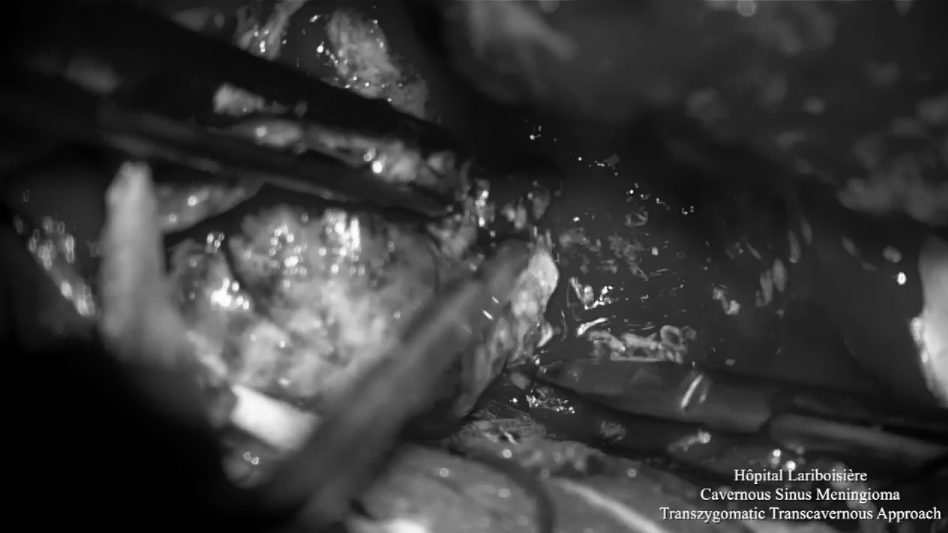

▼显微镜下切除部分肿瘤或瘤内减压

▼显微镜下暴露充分肿瘤,进行关键解剖定位